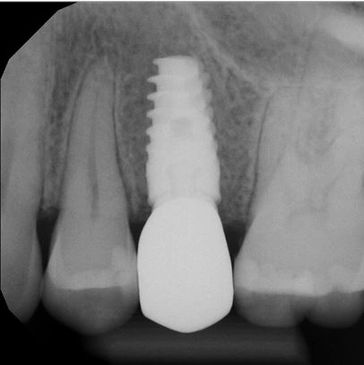

In our clinic, we use digital X-rays with the NOMAD portable unit and digital sensors to provide quick, high-quality images of your teeth. This technology minimizes radiation exposure and enhances diagnostic accuracy. The instant imaging allows for clear views and easy sharing, improving communication and efficiency in your dental care.